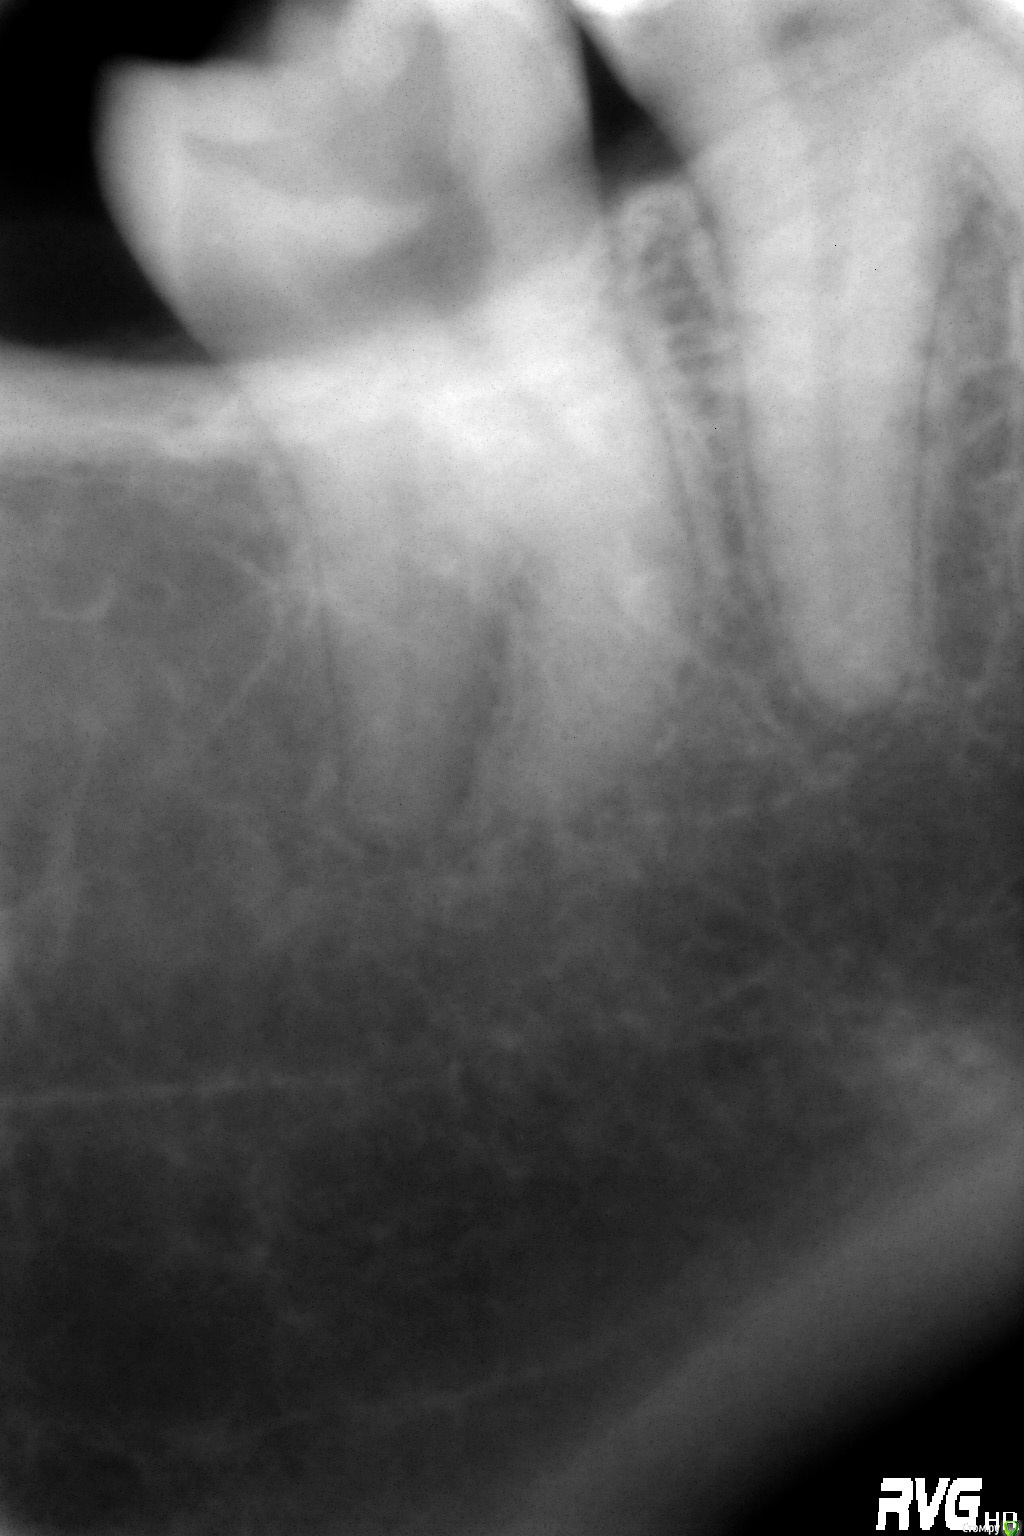

Kovalov Igor Опубликовано 26 марта, 2015 Поделиться Опубликовано 26 марта, 2015 48 и 49 зуб... пошел на удаление 48, откинул лоскут а там 49))) сделал потом Rg.49 вышел очень быстро, а 48 нет)) 7 Ссылка на комментарий

red_butler Опубликовано 26 марта, 2015 Поделиться Опубликовано 26 марта, 2015 сделал потом Rg снимки нужно делать до... 1 1 Ссылка на комментарий

Kovalov Igor Опубликовано 26 марта, 2015 Поделиться Опубликовано 26 марта, 2015 снимки нужно делать до... Ну там с виду обычная восьмерка была. Думаю Вы тоже не всегда делаете Rg при удалении ... Или ошибаюсь ? Ссылка на комментарий

Kev Опубликовано 26 марта, 2015 Поделиться Опубликовано 26 марта, 2015 Ну там с виду обычная восьмерка была. Думаю Вы тоже не всегда делаете Rg при удалении ... Или ошибаюсь ?8ки зубы-сюрпризы, так что всегда Rg делаю=))Хотя рентген тоже не панацея=)) Ссылка на комментарий

red_butler Опубликовано 26 марта, 2015 Поделиться Опубликовано 26 марта, 2015 Ну там с виду обычная восьмерка была. Думаю Вы тоже не всегда делаете Rg при удалении ... Или ошибаюсь ?у меня ОПГ обязательный элемент диагностики 3 Ссылка на комментарий

Jurai Опубликовано 26 марта, 2015 Поделиться Опубликовано 26 марта, 2015 А как вы обосновываете документально необходимость удаления? а тут фото приложил и все все поняли. И в клинике у нас правило - без снимка даже анестезию не делать. Ссылка на комментарий

Kovalov Igor Опубликовано 27 марта, 2015 Поделиться Опубликовано 27 марта, 2015 у меня ОПГ обязательный элемент диагностикихороший подход, просто снимок прицельный у нас делают так, что видна только коронка, верхушек корней 8ых зубов не видать и подавно, оптг другое дело) 1 Ссылка на комментарий

kladoffka Опубликовано 27 марта, 2015 Поделиться Опубликовано 27 марта, 2015 хороший подход, просто снимок прицельный у нас делают так, что видна только коронка, верхушек корней 8ых зубов не видать и подавно, оптг другое дело)Видимо наш рентгенолог к вам на подработку ездит - такая же ситуация) 2 Ссылка на комментарий